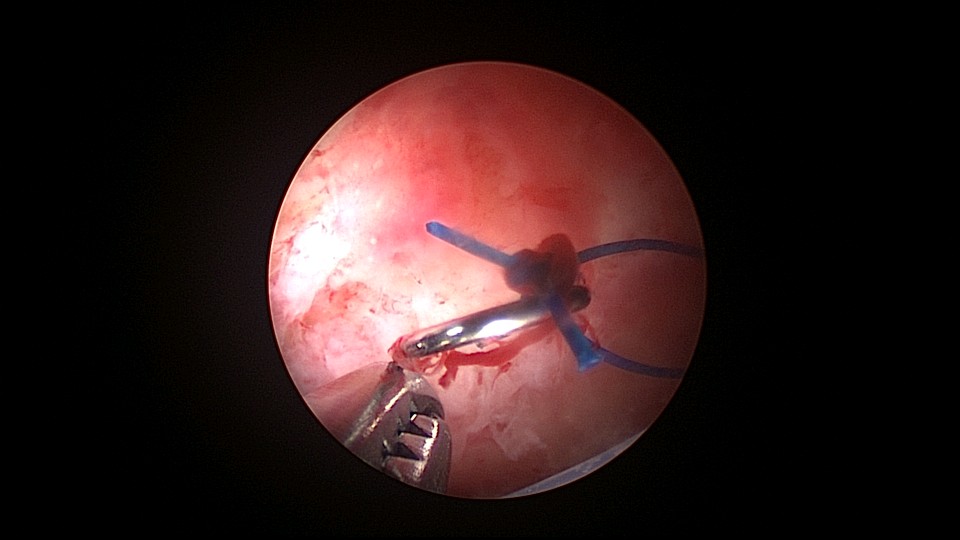

患者46岁,G2P2,顺产2次。因子宫腺肌症,严重痛经,8年前在江苏某医院放置曼月乐环,1+月后环脱落,未再继续治疗腺肌症,忍受了近7年痛经折磨。1+年前在外院再次放置曼月乐环,病人讲述手术医生做了环固定,最近月经量增多,痛经恢复至放环前,安环医院B超提示子宫后位,环已脱落,子宫7.4cm*7.4cm*8.4cm大小,朋友介绍到我院做曼月乐固定。宫腔镜见子宫后倾后屈位,宫深8.5cm,无法看到两侧宫角及子宫后壁,放弃缝合固定,用挂钩固定曼月乐环于宫底,先将不锈钢挂钩插入宫底肌层,4-0不可吸收线在曼月乐横臂中间套扎形成线圈,将曼月乐置入宫腔,异物钳夹持线圈挂到不锈钢挂钩里,原位固定曼月乐,退出宫腔镜,结束手术。术后多次复查B超,曼月乐位置正常,环顶端距宫底2.0cm。